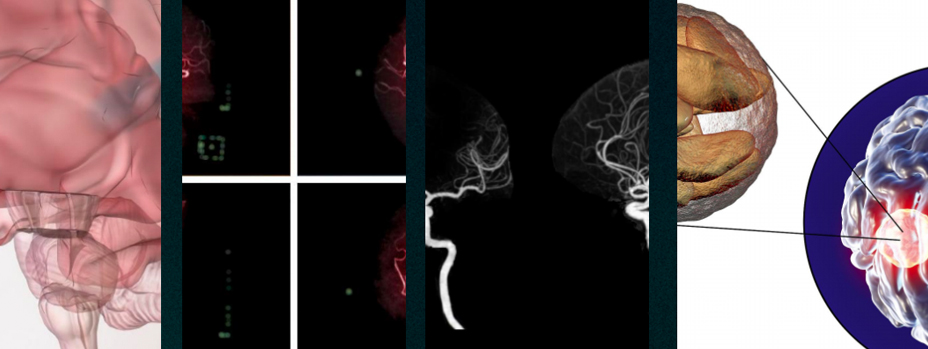

· 腦血管疾病

機(jī)制:臭氧可以改善血液流動性,增加紅細(xì)胞的攜氧能力,促進(jìn)腦部血液循環(huán),減少缺血再灌注損傷。

腦梗死:通過靜脈注射臭氧,可以改善腦部血液循環(huán),減少腦組織的缺血損傷,促進(jìn)神經(jīng)功能的恢復(fù)。

腦出血 : 臭氧可以減輕腦水腫,減少炎癥反應(yīng),有助于穩(wěn)定患者病情,促進(jìn)康復(fù)。